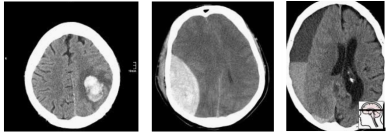

那么我们如何处理多重假设检验呢?一切都归结于问题的原因,那就是数据。Epi101 告诉我们,任何测试集都是目标群体的有偏版本。在这种情况下,目标人群是「所有 CT 头部成像的患者,有或没有颅内出血」。让我们来看看这种偏差是如何产生的,举一个假设人口很少的演示例子:

在这个人群中,我们有相当合理的「临床」病例组合。脑内出血 3 例(可能与高血压或中风有关),外伤性出血 2 例(右侧硬膜下出血,左侧硬膜外出血)。

现在,让我们对这个总体进行采样,以构建我们的测试集:

随机地,我们最终会有大部分额外的轴(大脑本身以外)出血。一个在这个测试中表现良好的模型不一定能在真实的病人身上发挥作用。事实上,你可能会期待一个模型,它真正擅长识别轴外出血。